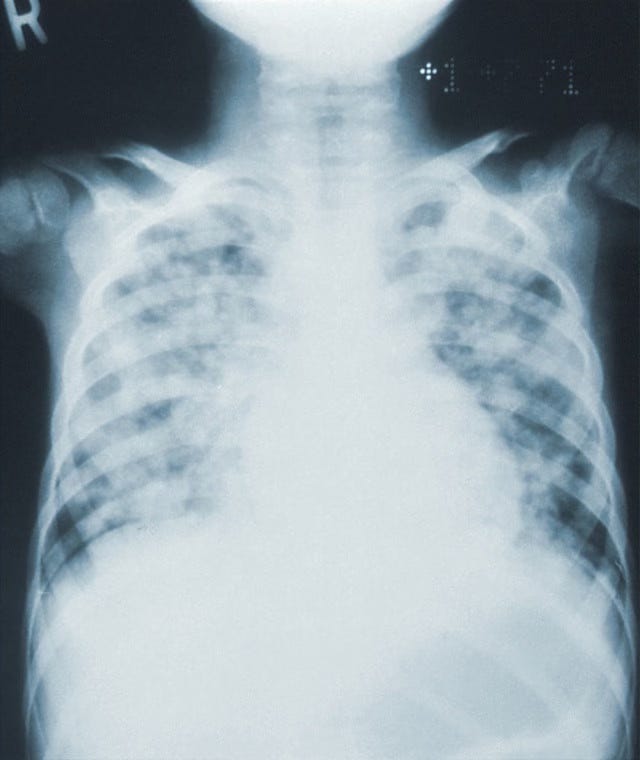

A recent study has shown that the use of antibiotic therapy during an influenza infection can damage the lung's defence against bacteria.

Antibiotic prescription for viral chest infections is unfortunately commonplace. This is partly due to clinician factors such as misdiagnosis or uncertainty, but is greatly influenced by patient pressure. Apart from the fact that such prescribing will have no beneficial effects upon the clinical course of the infection, there is also the possibility of detrimental effects such as increasing microbial antibiotic resistance, so encouraging the emergence of 'superbugs', and weakening the patient's defences to further bacterial infection. The study focused upon the latter.